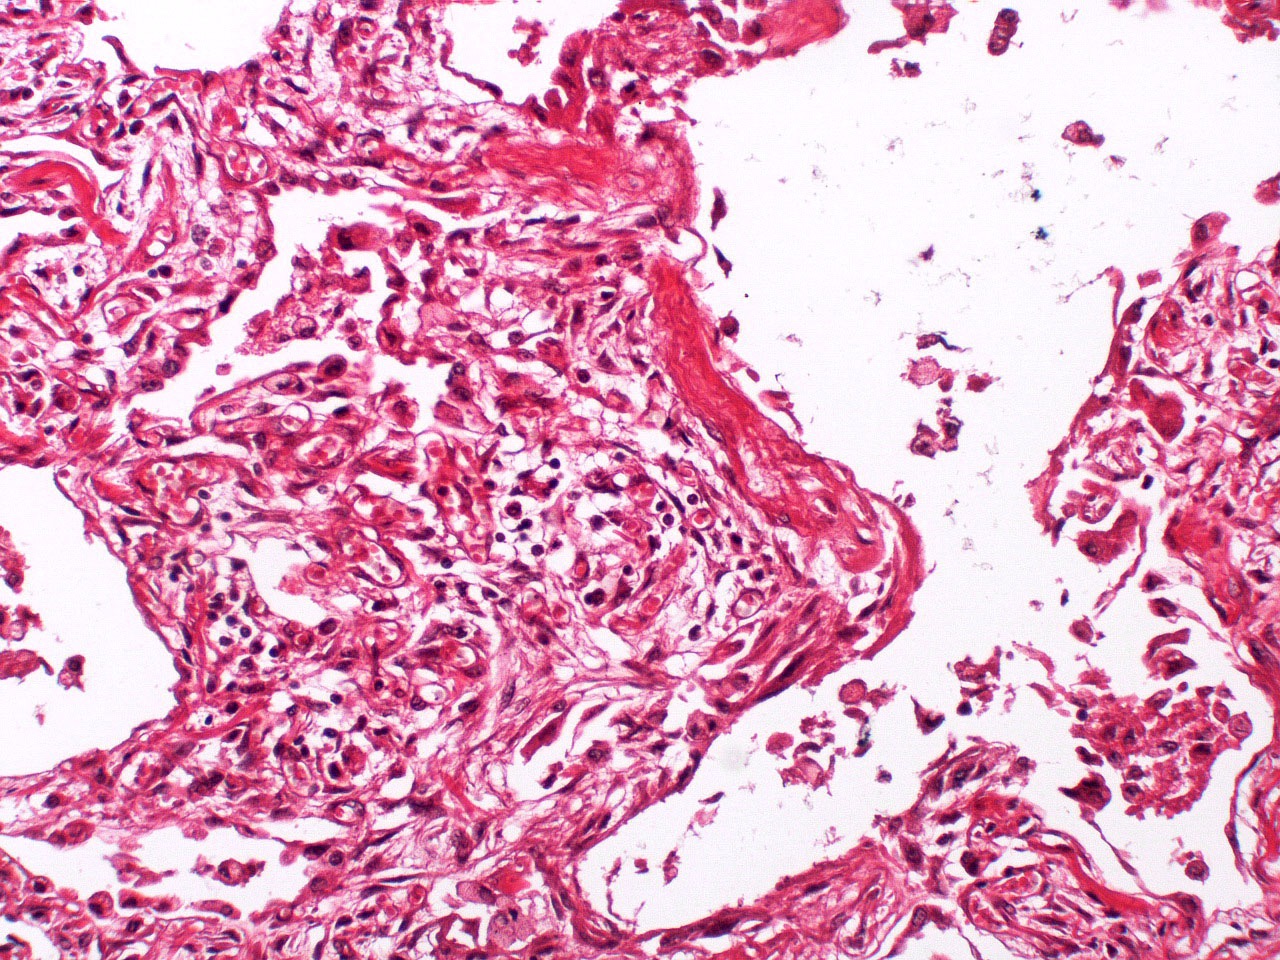

Microscopic (histologic) description

- Histopathology of DAD progresses from exudative (acute) phase through proliferative / organizing (subacute) phase to chronic fibrotic phase roughly corresponding to the period of ARDS (Am J Pathol 1976;85:209, Arch Pathol Lab Med 2010;134:719, Clin Chest Med 2000;21:435, N Engl J Med 2000;342:1334)

- Exudative (acute) phase

- Alveolar change

- Hyaline membranes on alveolar duct or sacs

- Interstitial and intra-alveolar edema

- Collapsed alveoli

- Epithelial change

- Denudation and necrosis of type I pneumocytes

- Vascular change

- Necrosis of endothelial cells

- Neutrophil aggregation

- Microthromboemboli

- Hemorrhage

- Alveolar change

Microscopic (histologic) images

Contributed by Akira Yoshikawa, M.D. and Yale Rosen, M.D.